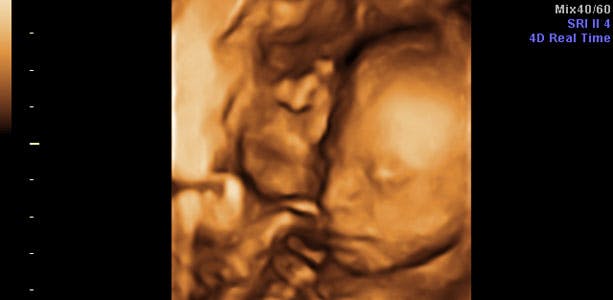

Gravid uge 22: Tynd og rynket hud

Huden er fortsat tynd og rynket, fordi den vokser meget endnu, uden at der er kommet et fedtlag under til at give fylde i kinderne. Ansigtet kommer derfor nemt til at ligne en gammel bekymret kvinde eller mand. Hudfarven er rødlig på grund af de tydelige blodkar. I slutningen af ugen måler barnet cirka 25 centimeter og vejer omkring 600 gram. Hovedet måler cirka 5,3 centimeter i diameter. Lårbensknoglen måler cirka 3,6 centimeter